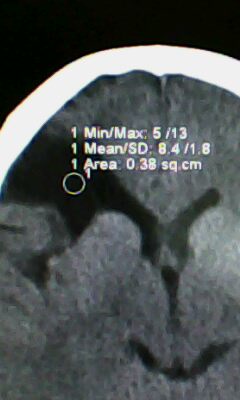

标题: CT25171:患者间断性头痛 无外伤史 [打印本页]

标题: CT25171:患者间断性头痛 无外伤史

右侧额叶脑穿通畸形囊肿。

右侧额叶脑穿通畸形囊肿。支持!